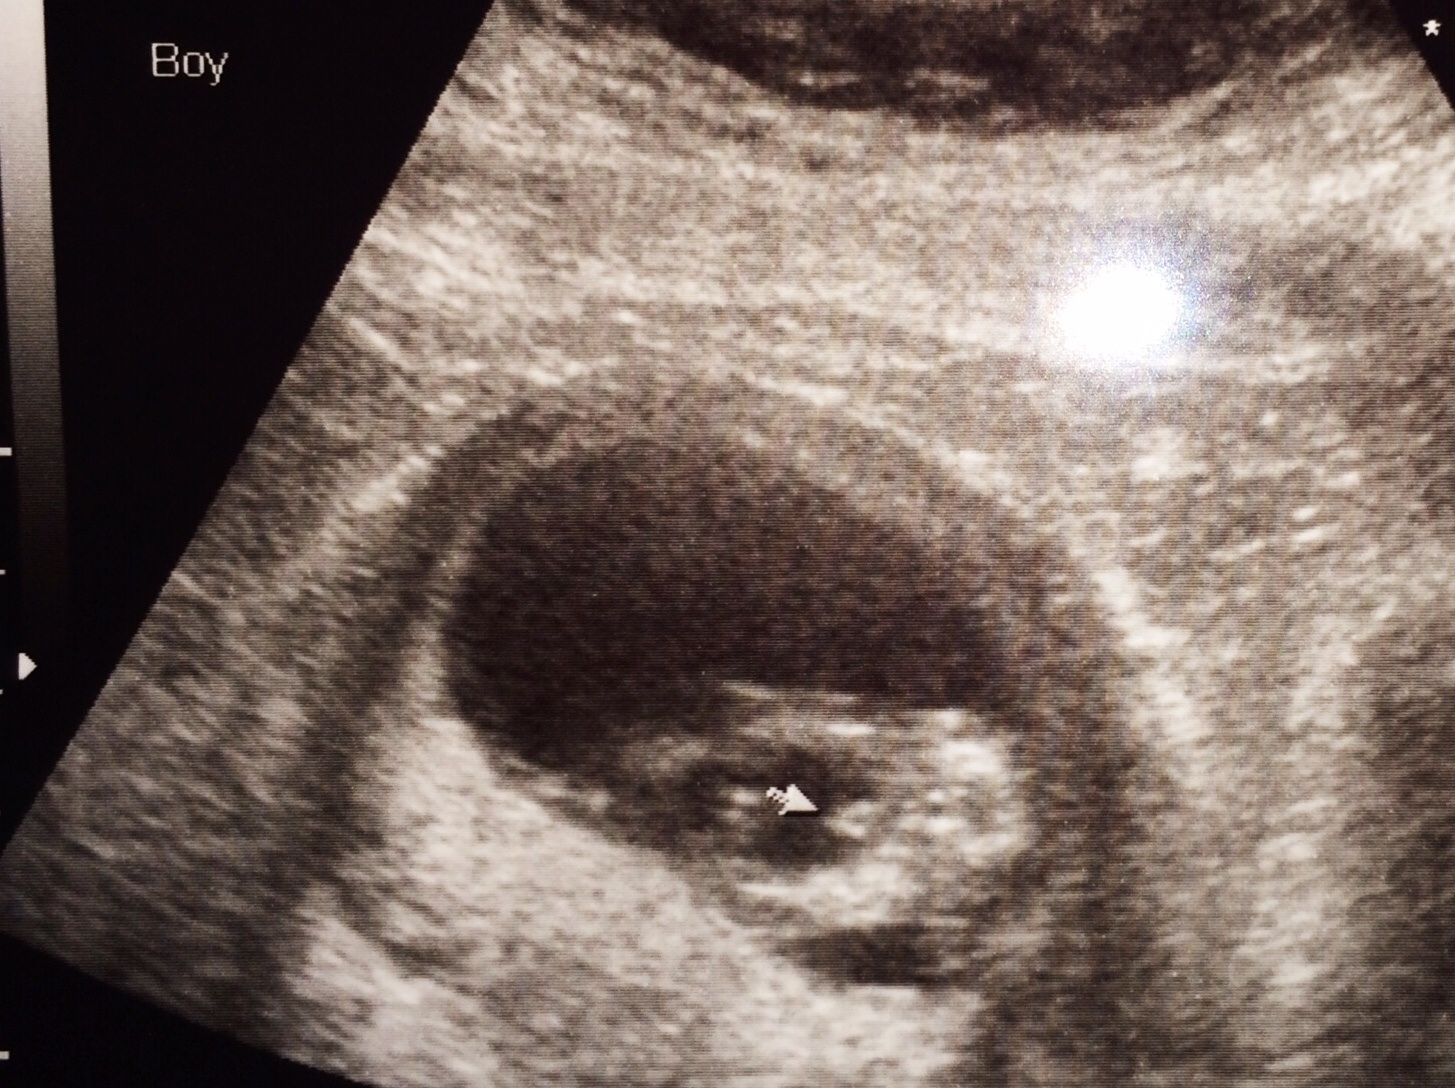

We had out NT scan today. It was AMAZING! We got to see the prawn wiggling around and waving at us! And midway through, the u/s tech asked if we wanted to know the sex! I didn't even think you could tell this early, but the prawn was quite accommodating and our tech said we're having a boy!

She is apparently about 95% accurate, according to my doctor, my mom (the head midwife at the practice), and all the nurses. And she wouldn't have said anything at all if she wasn't confident. Of course, we will confirm at the anatomy scan.

Plusalso, have an ultrasound of the prawn's bottom, lol!

• Congrats! I asked at our NT scan this morning and was just told it's too early to tell lol. The tech went over the butt part like you have in the photo and I didn't see anything in between the legs so I'm rooting girl ;) obviously know it's not reliable but I'm teasing H about having another one of me around